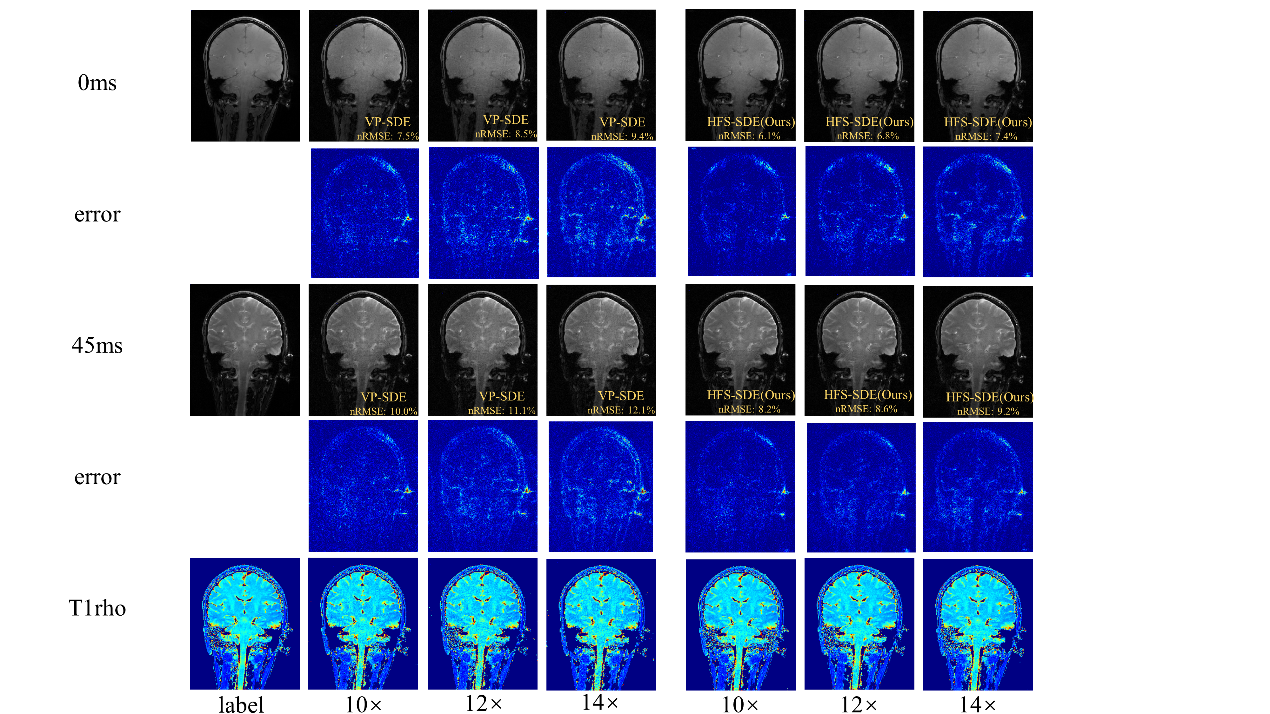

在超高場功能磁共振T1ρ弛豫定量成像方面,團隊首次在5.0 T磁共振平臺上測試了大腦T1ρ成像的可行性,并比較了使用3.0 T和5.0 T掃描儀所得的T1ρ值。實驗結(jié)果表明,5.0T下獲得了信噪比更高的T1ρ加權(quán)圖像。在高分辨率成像中,5.0T的信噪比優(yōu)勢更明顯。該成果發(fā)表在Frontiers in Physics(2022,10:1016932)。團隊還提出一種用于基于擴散的MR重建方法——HFS-SDE,并將這種新方法應(yīng)用于MR T1ρ映射,實現(xiàn)14倍的高加速度,相對于VP-SDE的高速倍數(shù)下沒有顯示偽影,nRMSE值明顯優(yōu)于VP-SDE,并且圖像的高頻細節(jié)得到了更好的重建,該成果“Diffusion generative prior-based highly accelerated MR T1ρ mapping”在2023 ISMRM會議被收錄為Power Pitch。

圖4 團隊提出的HFS-SDE方法不僅提高了擴散模型的穩(wěn)定性,并在5T時實現(xiàn)了T1ρ定量成像的高加速,而且更準確地恢復(fù)MR圖像中的高頻細節(jié)。